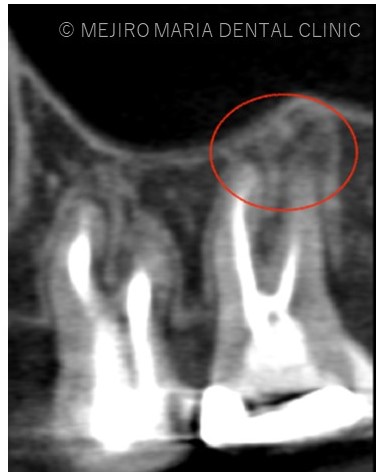

右上7番には臨床症状(叩くことでの痛み)が確認できるものの、レントゲン上には根尖性歯周炎と判断できる透過像(病変の影)は確認できませんでした。歯科用CTを撮影してみると、近心根と遠心根に明らかな病変を認めました(歯科用CT画像1赤丸)。他の臨床症状と歯科用CT画像から右上7番の根尖性歯周炎と診断しました。

また、同時に近心根には見逃している根管もしくはフィンと言われる極小なスペース(CT画像2赤丸)が存在することも確認できます。